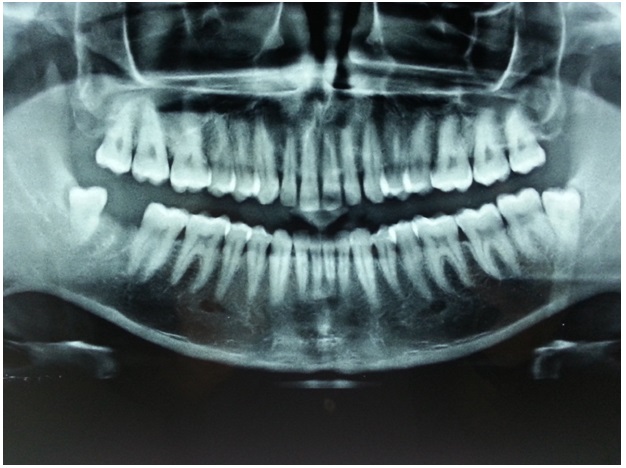

A 24-year-old healthy male visited our private clinic in Bangalore with chief complaint of pain and discomfort in lower right back teeth region since 4-5 days. On intraoral examination, soft tissues which covered 3/4th of occlusal (distocclusal) surfaces of 48 appeared to be moderately inflamed and the other entire oral tissues appeared to be normal. An IOPA radiograph in relation to 47, 48 was taken and a diagnosis of a partially impacted (soft tissue impaction) third molar with pericoronitis was given. The patient was advised surgical removal of third molar, for which he gave his consent. Third molar extraction was planned and it was successfully done under local anaesthesia, based on IOPA radiograph, but intra operatively, distal to third molar, a globular mass of enamel like glossy appearance was observed, which prompted us to investigate further by orthopantomography (OPG). OPG revealed impacted, bilateral, mandibular fourth molars [Table/Fig-1]. Considering the possible complications, both the distomolars were planned to be surgically removed after obtaining the patient’s consent. The distomolars were of supplemental type, which resembled third molars. After one week, post-operative oral examination revealed uneventful healing. Anna KS called them as “ghost tooth” which had evolved from behind third molars [1].

OPG revealing impacted mandibular bilateral 4th molars